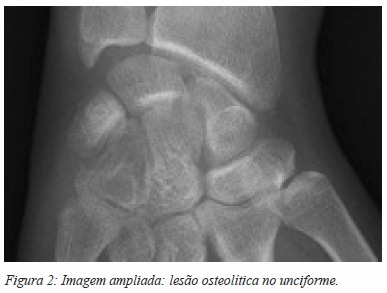

Apresentava radiografia (Figuras 1 e 2) com lesão lítica do unciforme, com esclerose dos bordos, sem disrupção da cortical, que ocupava cerca de 30% do osso. Foi pedida uma TC, que revelou uma lesão ocupando espaço do unciforme.

A hipótese diagnóstica, pela aparente não agressividade da lesão e dada a elevada prevalência, era a de um encondroma. Foi submetida a cirurgia de remoção da lesão. Por via dorsal, foi curetada a lesão com colocação de enxerto esponjoso de ilíaco e fosfato de cálcio. A recuperação decorreu sem intercorrências, com recuperação progressiva da mobilidade do punho. O controlo radiográfico da cirurgia está ilustrado nas figuras 3 e 4.